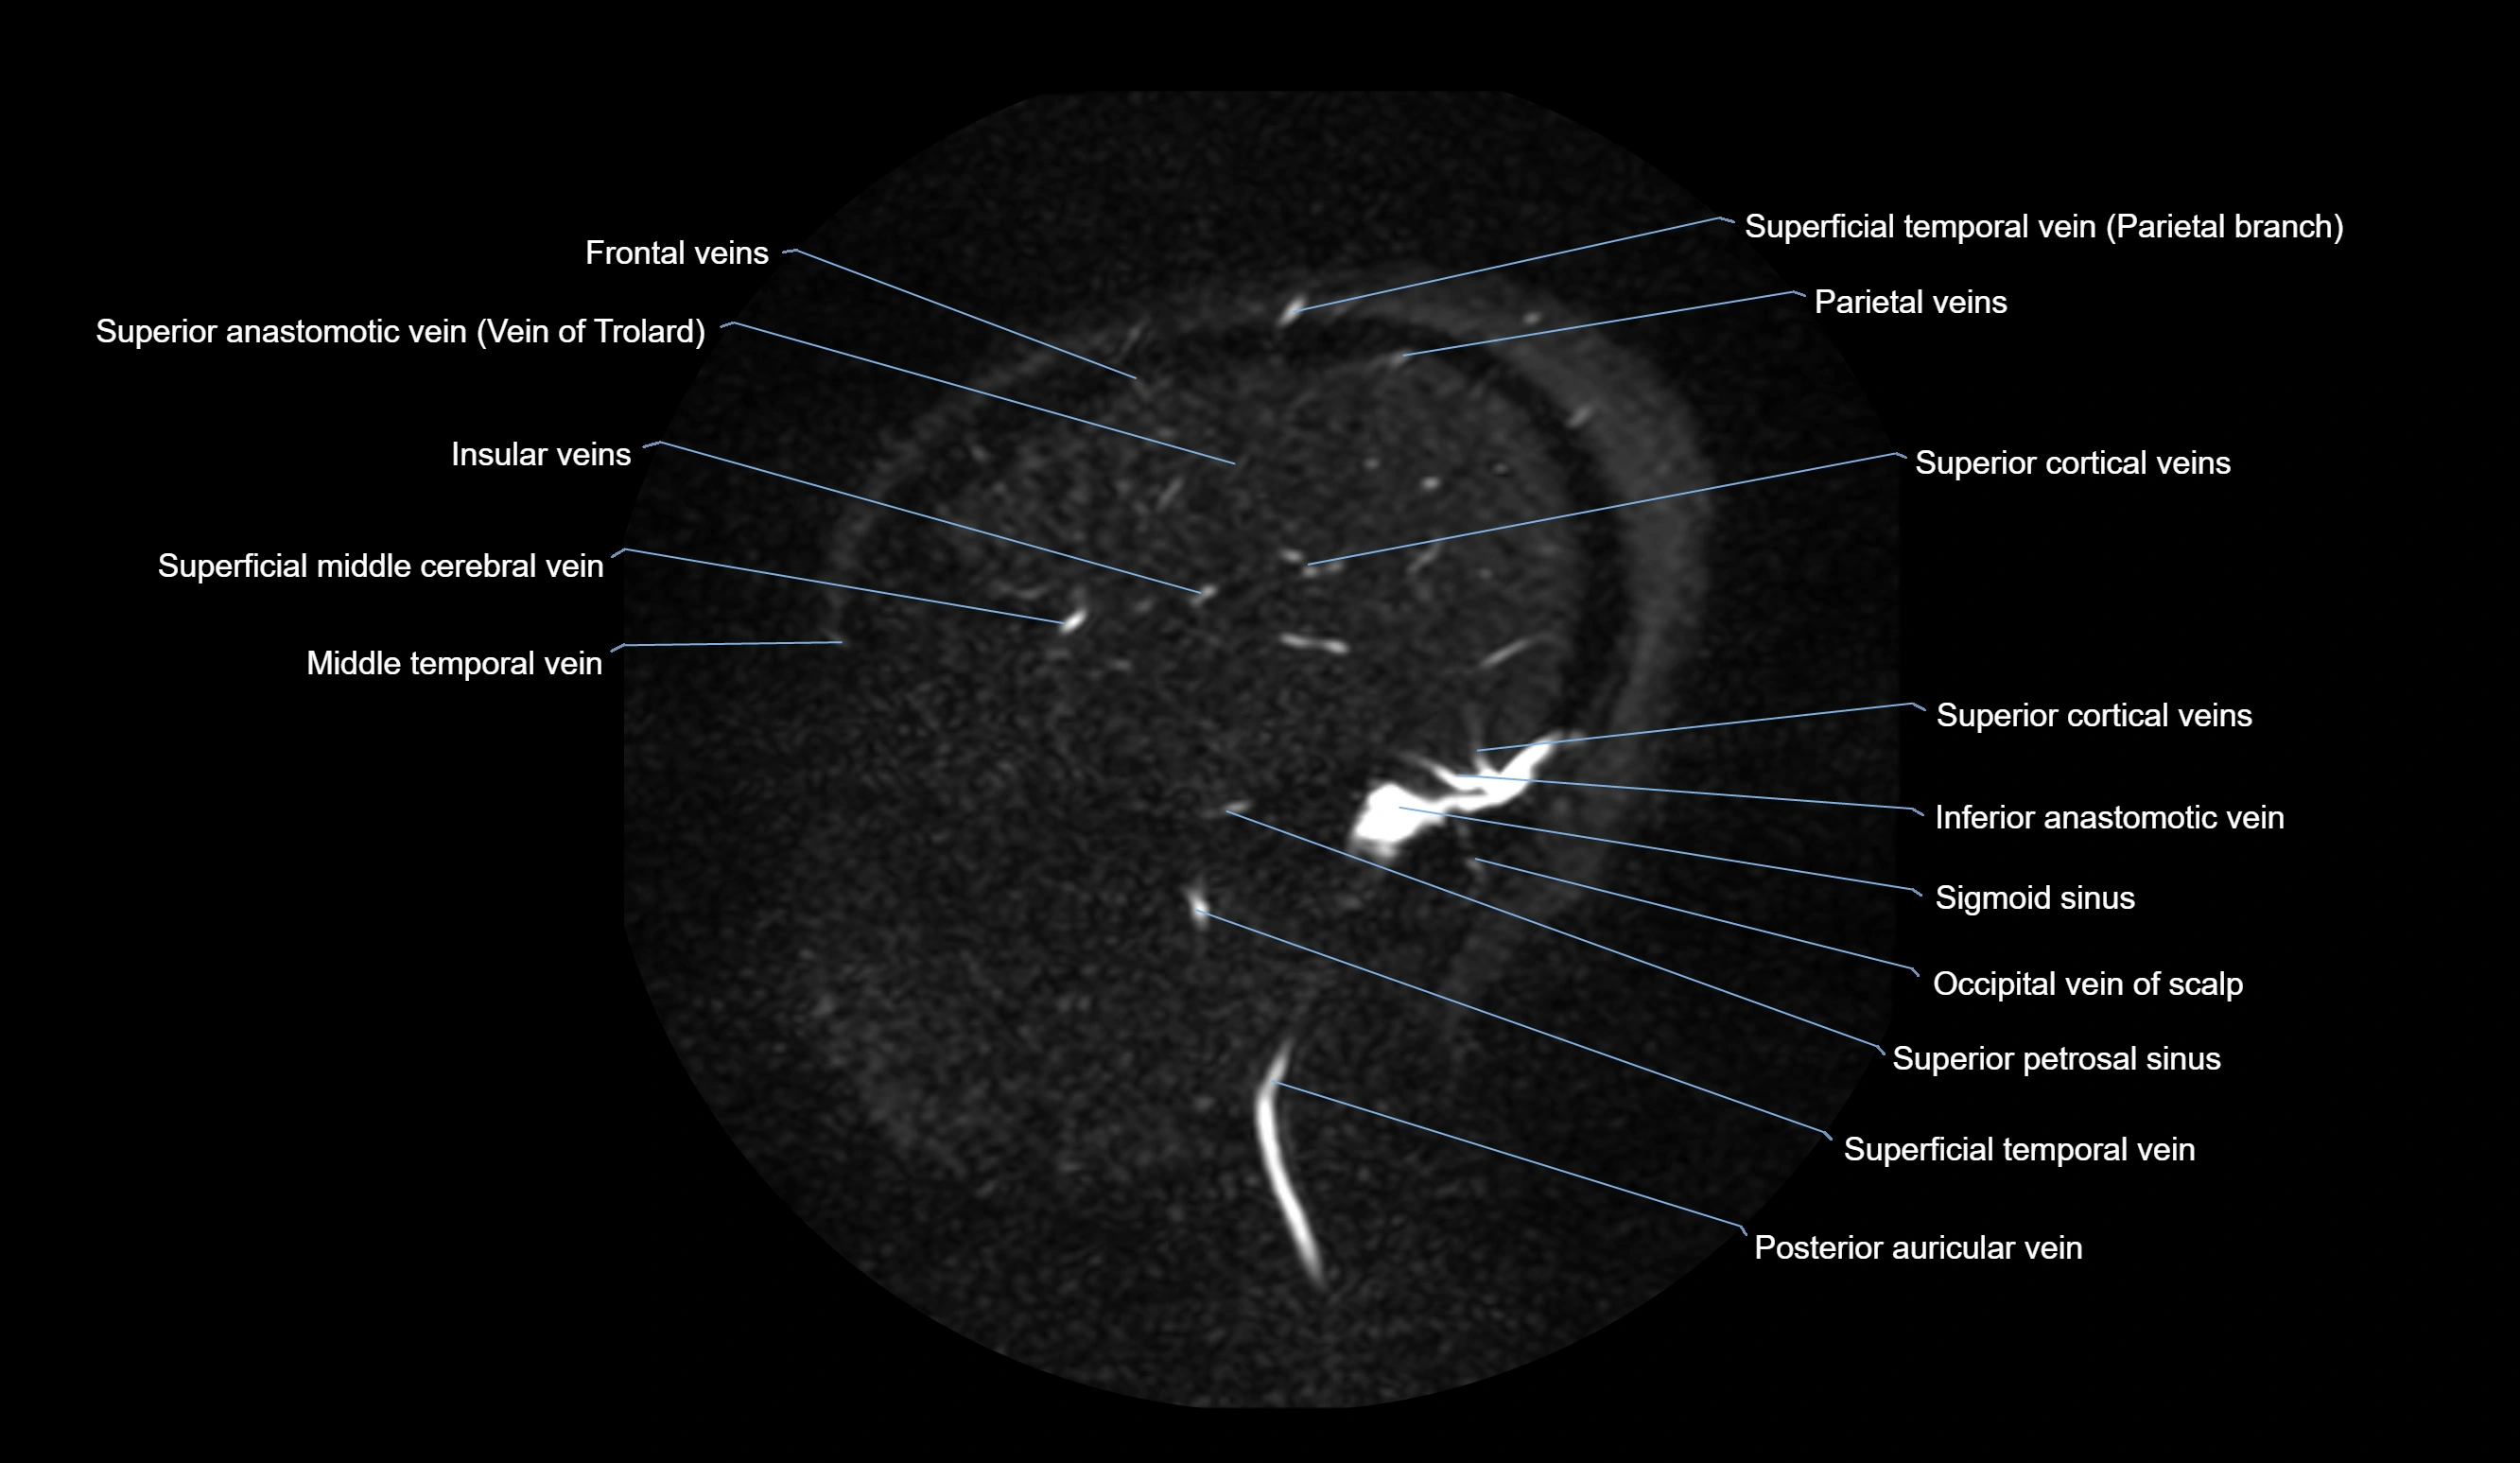

CT Venography (CTV):

• Clearly visualizes the angular vein as a contrast-filled venous channel

• Demonstrates its communication with the facial vein, superior ophthalmic vein, and cavernous sinus

• Essential for detecting facial vein thrombosis, orbital venous involvement, and cavernous sinus pathology